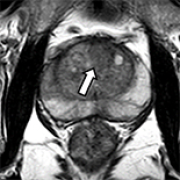

Combining Magnetic Resonance Diffusion-Weighted Imaging with Prostate-Specific Antigen to Differentiate Between Malignant and Benign Prostate Lesions

Liying Han, Guanyong He

DOI: 10.12659/MSM.935307

Med Sci Monit 2022; 28:e935307